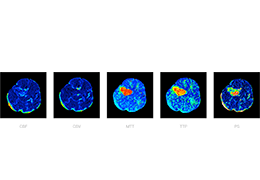

ART-Plan™ Artificial Intelligence Contouring